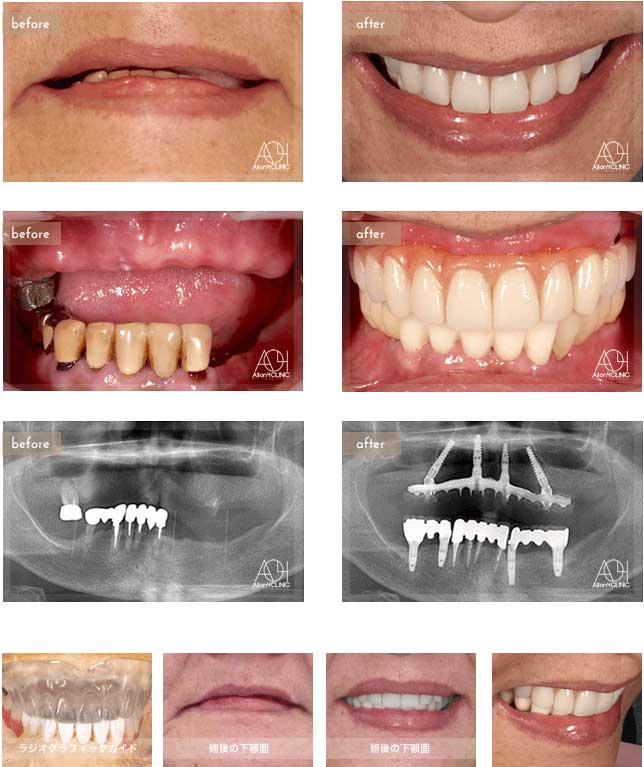

Treatment : All-on-4

- Upper All-on-4

- Lower All-on-4

Age : 62 Sex : 女 Y.M

| 主訴 | 入れ歯が合わなく痛いし、入れ歯を入れている事が嫌になってしまった。 |

| 治療内容 | X-guide(エックスガイドナビゲーションシステム)を用いてインプラントを正確に埋入。 上下オールオン4。 |

| 治療費(総額) | ¥7,200,000(税抜)『モニター割引適用』 |

| リスク | 治療後の口腔管理が不適切な場合、埋入したインプラント周囲に感染・炎症を起こし、脱落する可能性がございます。 |